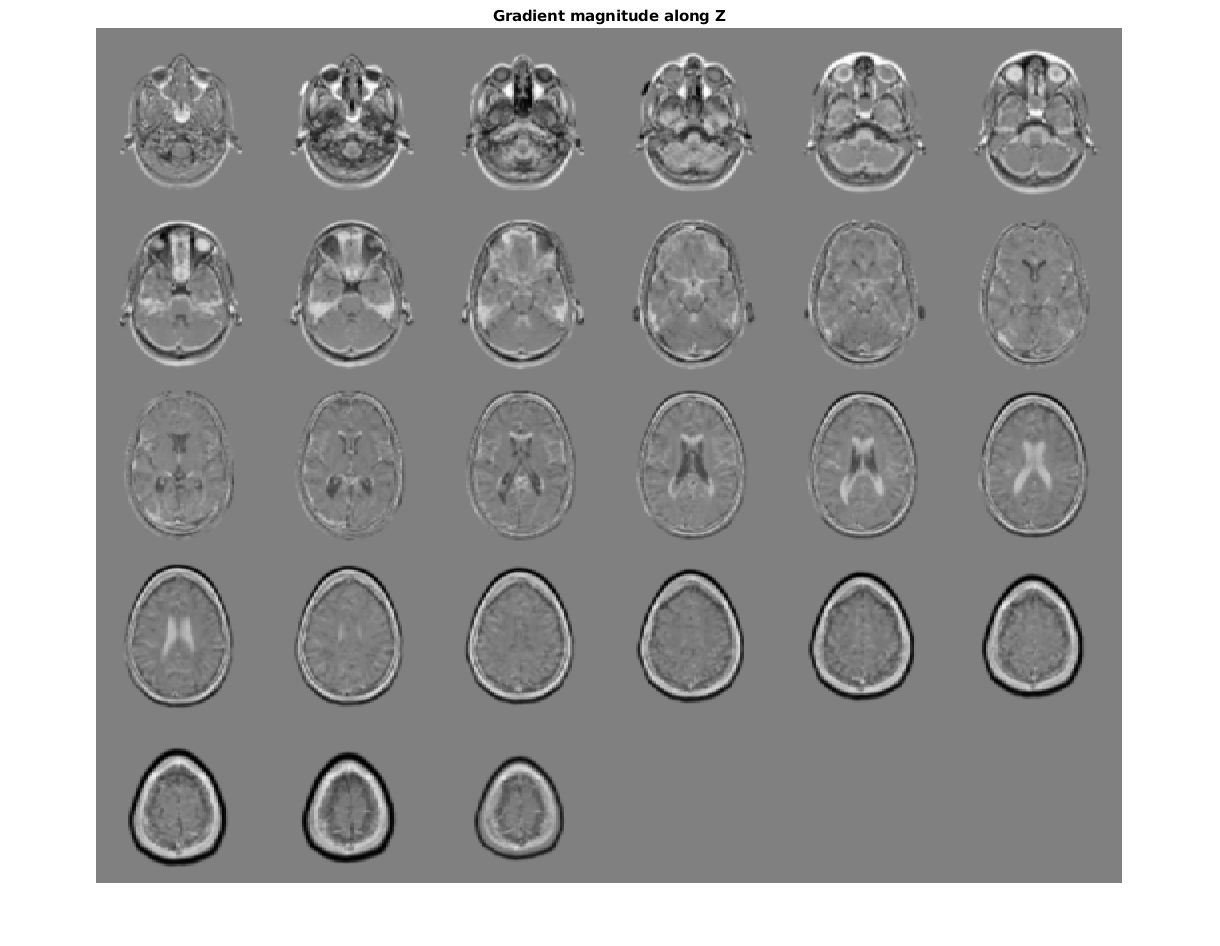

figure, montage(reshape(Gz,sz(1),sz(2),1,sz(3)),'DisplayRange',[])

title('Gradient magnitude along Z')

Figure contains an axes. The axes with title Gradient magnitude along Z contains an object of type image.